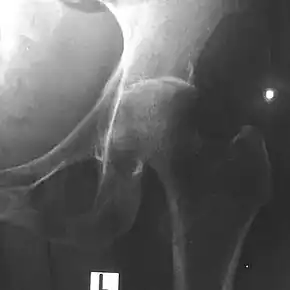

Depending on the course of infection, other severe manifestations develop. About 1 to 5% of those infected develop inflammation of the brain and brain covering or collection of pus in the brain; 14 to 28% develop bacterial inflammation of the kidneys, kidney abscess or prostatic abscesses; 0 to 30% develop neck or salivary gland abscesses; 10 to 33% develop liver, spleen, or paraintestinal abscesses; 4 to 14% develop septic arthritis and osteomyelitis.[2] Rare manifestations include lymph node disease resembling tuberculosis,[10] mediastinal masses, collection of fluid in the heart covering,[4] abnormal dilatation of blood vessels due to infection,[2] and inflammation of the pancreas.[4] In Australia, up to 20% of infected males develop prostatic abscess characterized by pain during urination, difficulty in passing urine, and urinary retention requiring catheterisation.[2] Rectal examination shows inflammation of the prostate.[4] In Thailand, 30% of the infected children develop parotid abscesses.[2] Encephalomyelitis can occur in healthy people without risk factors. Those with melioidosis encephomyelitis tend to have normal computed tomography scans, but increased T2 signal by magnetic resonance imaging, extending to the brain stem and spinal cord. Clinical signs include: unilateral upper motor neuron limb weakness, cerebellar signs, and cranial nerve palsies (VI, VII nerve palsies and bulbar palsy). Some cases presented with flaccid paralysis alone.[4] In northern Australia, all melioidosis with encephalomyelitis cases had elevated white cells in the cerebrospinal fluid (CSF), mostly mononuclear cells with elevated CSF protein.[10]